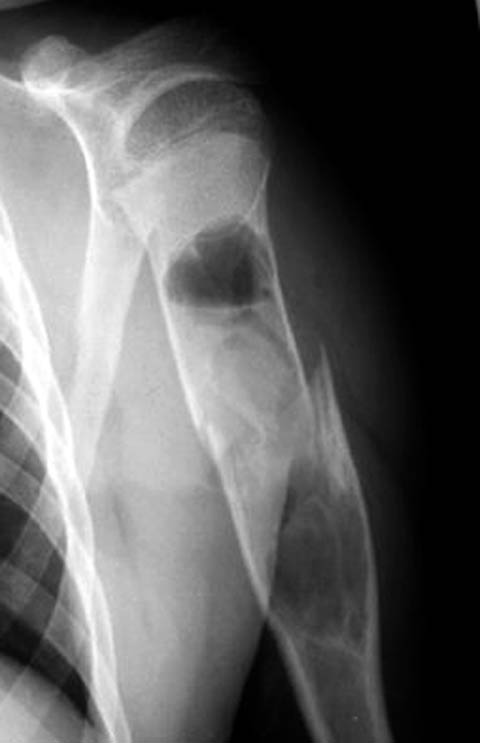

Рентгенологически патологический перелом шейки левой плечевой кости,

Обычный перелом с адекватным механизмом.

наличие секвестра,

Где Вы видите секвестр и что под этим термином подразумеваете? Может быть Вы имеете ввиду небольшой (2х1,5 см) отломок?

шаровидная полость в головке.

Это не шаровидная полость, а нормальное рентгеновское изображение ротированного проксимального отломка

Сегодня сделал контрольный снимок места перелома и дествительно отломок, который я принял за секвестр изменился, хотя полость возможной кисты сохраняется. Спорным остается наличие шарополости в головке плеча. Сделал также и противоположный сустав для сравнения. Возможности КТ в моей ЦРБ не имеется. В обласной центр ( 100 км. ) потерпевший ехать не очень стремится.

Данная полость на стороне поражения очень напоминает полость аневризмальной кисти. Кто нибудь втречал такую патологию у взросхих?

Это не полость и не секвестр. Остеопороз головки плечевой кости и фрагмент.С противоположной стороны (другая проекция)также зона остеопороза в области большого бугорка.

Дифференциальную диагностику надо проводить между однокамерной костной и аневризмальной кистой, но расположение в полости кисты тонкого,

линейного фрагмента кости, подтверждает диагноз однокамерной костной кисты.

"Упавший" фрагмент - патогномоническая подсказка к патологическому перелому, часть стенки падает в полость кисты и опускается вниз из-за

силы тяжести.

Подозрение о "шаровидной полости" в головке - это из-за укладки, и на представленном снимке подтверждение правильности рекомендации коллег.